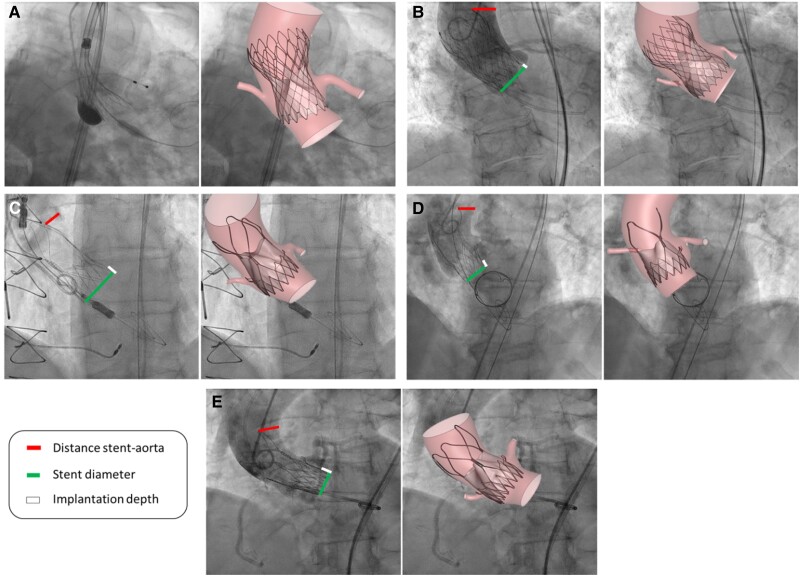

Methods and results: Five patients with BAV undergoing TAVI were enrolled. TAVs were virtually modelled within each BAV patient-specific anatomy, resulting in 10 virtual patients. Acurate Neo2 and Evolut R implantations were subsequently simulated across all cases. Post-implantation stresses exerted on both the stent and aortic root were measured, allowing a comparative analysis of the impact of the two valve morphologies. Comparing stent stresses between BAV and TAV configurations, the stress gap increased by 21.96 ± 5.35% (P = 0.01) in Acurate Neo2 cases (n = 6) compared with Evolut R cases (n = 4). The analysis of aortic root stresses showed no significant differences between BAV (n = 5) and TAV (n = 5) configurations, with a mean stress difference of 5.1 ± 8.17% (P > 0.05).